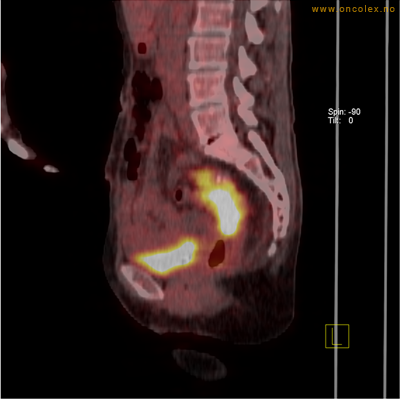

Eksempler på funn

Vev som tar opp mer radioaktivt stoff, synes som hvite områder som lyser opp mer i forhold til annet vev som tar opp mindre sukker.

Adenokarsinom distalt i spiserør. Fysiologisk opptak i hjertemuskulatur.

Adenokarsinom langt nede i spiserøret.

Høyt opptak av 18F-FDG i adenokarsinom i rektosigmoideumovergangen. Fysiologisk opptak i blæren.